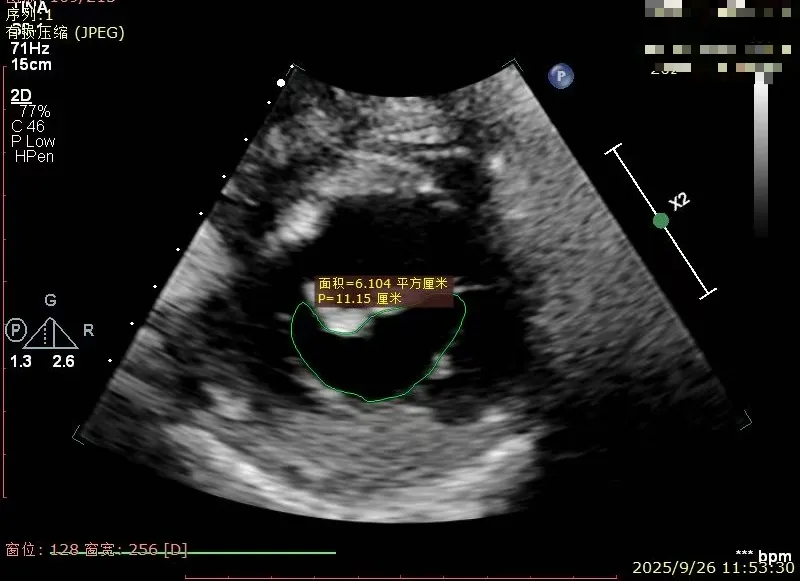

经胸超声报告提示:患者二尖瓣2区及3区前叶关闭时脱入左房,二尖瓣重度反流(MR 4+),患者LA前后径约52mm,LVEDD约68mm,LVESD约42mm,EF值:65%,经胸超声测二尖瓣瓣口面积约6.1cm2,主动脉瓣无冠瓣脱垂并中重度反流,三尖瓣中度反流,估测中度肺动脉高压。

经胸短轴测得瓣口面积约6.1cm2